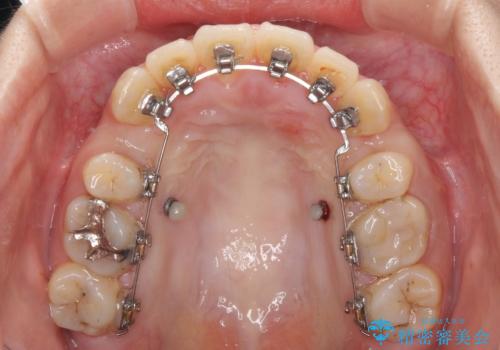

- ハーフリンガル

目立たない装置を希望されたので、上顎が裏側装置のハーフリンガルを選択し、上下左右の小臼歯(計4歯)を抜歯して矯正治療を行うこととしました。

また、左下の奥歯は抜歯が必要な歯であったため、矯正治療中の良いタイミングで抜歯とインプラント埋入を行い、矯正治療後にオールセラミッククラウンで補綴治療を行うこととしました。

デコボコの解消までは非常にスムーズでしたが、咬合力が強いためか、スペースを閉じるまでに長い期間を要しました。

矯正治療途中にインプラント埋入と仮歯の装着を行ったことで、しっかりとした奥歯の咬み合わせで終了させることができました。